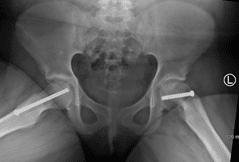

In this X-ray, two screws have been inserted in the patient's right hip to stop progression of a slip. A single screw has been inserted in the left hip to prevent SCFE from developing.